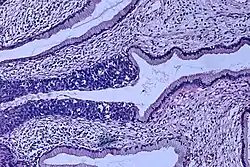

The naming and histologic classification of cervical carcinoma precursor lesions has changed many times over the 20th century. The World Health Organization classification system was descriptive of the lesions, naming them mild, moderate, or severe dysplasia or carcinoma in situ (CIS).[68][69] The term cervical intraepithelial neoplasia (CIN) was developed to place emphasis on the spectrum of abnormality in these lesions and to help standardize treatment.[69] For premalignant dysplastic changes, cervical intraepithelial neoplasia grading (CIN 1–3) is used. It classifies mild dysplasia as CIN1, moderate dysplasia as CIN2, and severe dysplasia and CIS as CIN3.[70] More recently, CIN2 and CIN3 have been combined into CIN2/3. These results are what a pathologist might report from a biopsy.

Invasive squamous cell carcinoma of the cervix is characterized by infiltration as irregular anastomosing nests or single cells.[75] This case is poorly differentiated. H&E stain. -

Cervical squamous cell carcinoma generally shows diffuse staining of both nuclei and cytoplasm on p16 immuno-

histochemistry (except verrucous variant).[76] -

Invasive cervical squamous cell carcinoma on H&E histopathology and Ki-67 immunohistochemistry. The latter correlates well with the degree and level of dysplasia.[77] -